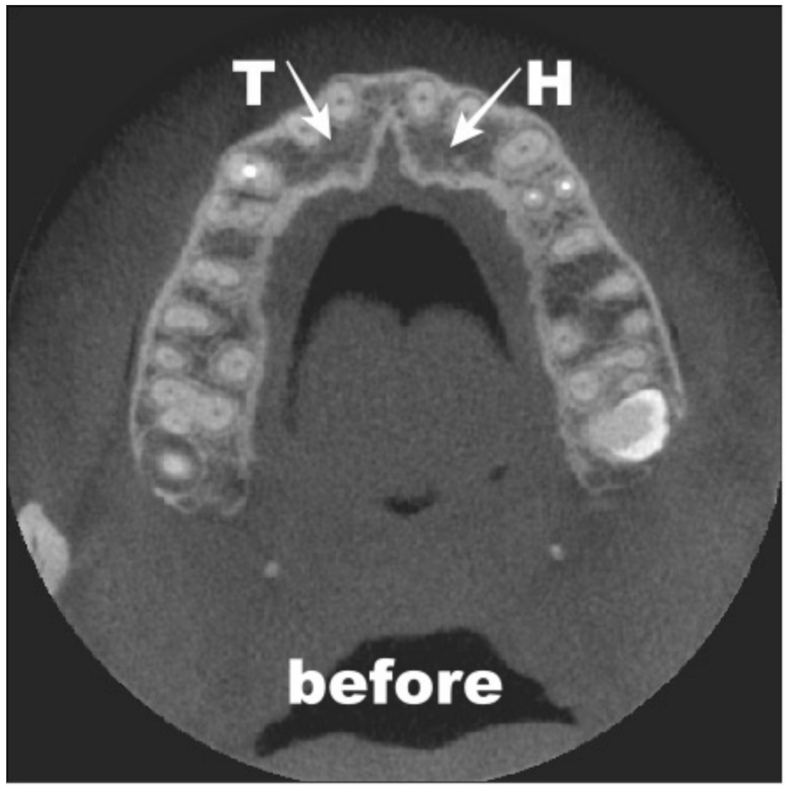

3. Materials and Methods

4. Results